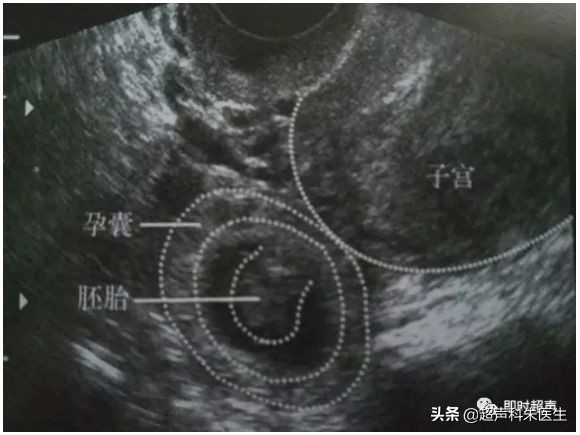

正常早孕及流产

正常早孕:宫腔内见到低回声的孕囊,其内见到卵黄囊,甚至是胚芽,可见原始心管搏动。

正常早孕